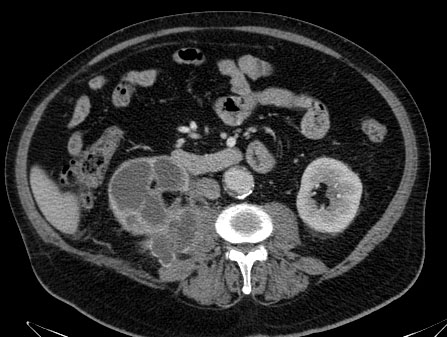

CASO 1: Paciente de 58 años que se realiza TC de abdomen tras historia de dolor abdominal y hematuria microscópica. Refiere pérdida de peso en las últimas semanas.

Estamos ante una afectación bilateral del espacio perirrenal, más evidente en el lado derecho, por masas de densidad de partes blandas en un paciente con numerosas adenopatías retroperitoneales. Estaría indicado realizar una biopsia, ya que el diagnóstico principal orienta hacia un síndrome linfoproliferativo, espcialmente linfoma no Hodgkin tipo B.

2. LINFOMA.

El linfoma renal presenta una gran variedad de manifestaciones. Entre un 3 y un 8 % de linfomas estudiados por TAC tienen afectación renal o perirrenal, más frecuentemente el tipo no Hodgkin.

Patrones de afectación del linfoma renal:

- Multiples masas renales en el riñón (+frecuente)

- Lesión solitaria.

- Adenopatías retroperitoneales con extensión directa a riñón y EPR (nuestro caso de hoy).

- Afectación del espacio perirrenal aislada.

- Infiltración difusa de uno o ambos riñones.

En el caso de que el linfoma afecte al EPR, se ve como una masa homogénea que ocupa este espacio y que desplaza el riñón hacia adelante, ocupando a menudo también el espacio pararrenal anterior. La afectación aislada del EPR por el linfoma es poco frecuente (<10%), es más común la extensión directa desde las adenopatías o grandes conglomerados/masas retroperitoneales (+frec) o la extensión desde el riñón.